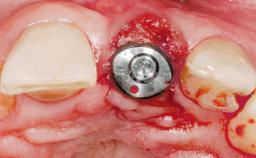

A 30-year-old female patient had lost tooth 21 and was referred to our clinic for consultation and treatment. Due to advanced apical infection, tooth 21 had been extracted two months earlier at another clinic and an acrylic-resin tooth had been bonded to the adjacent teeth. The patient desired implant treatment to avoid any damage to the adjacent natural teeth. While the patient had no history of any systemic disorder, she was a heavy smoker and exhibited medium to advanced periodontitis in the entire jaw. After the initial treatment to achieve a pocket probing depth of less than 4 mm and no bleeding on probing, a decrease in the height of the papillae mesial and distal to the extraction site and overall gingival recession were observed.

Type of Implants One-Piece|Reduced-Diameter

Placement Protocol Early or late implant placement

Bone Volume Deficient horizontally, requiring prior grafting